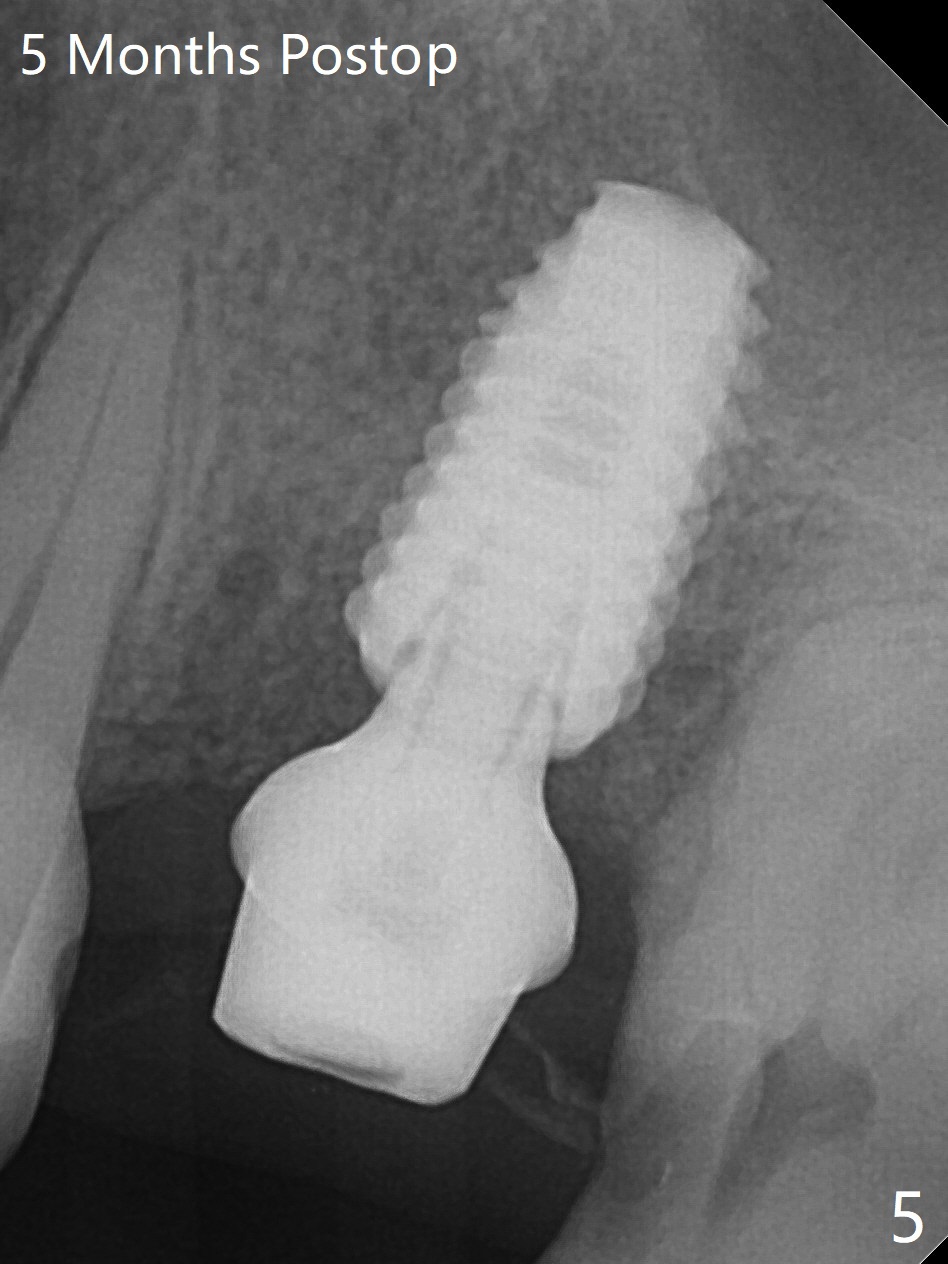

After removal of granulation tissue from the sockets associated with the fractured tooth at #14 (Fig.1 (* granulation tissue)) and initial osteotomy in the septum with a 2 mm drill for 8.5 mm, the sinus floor is penetrated by a parallel pin (Fig.2). But the sinus membrane remains intact until osteotomy finishes with a 4.8 mm drill. Following sinus lift with Vera Graft with autogenous bone (Fig.3 red *), a 5.5x10 mm implant is placed ~ 1 mm coronal to the septal crest and 1-3 mm apical to the surrounding crest (mesiodisto-buccopalatal, >55 Ncm). After further bone graft around the implant (Fig.3 white *), a 6.5x4(3) mm abutment is inserted with the 3rd round of grafting (Fig.3,4 black *). An immediate provisional is fabricated to keep the allograft in place. The implant seems to have osteointegrated 5 months postop (Fig.5).